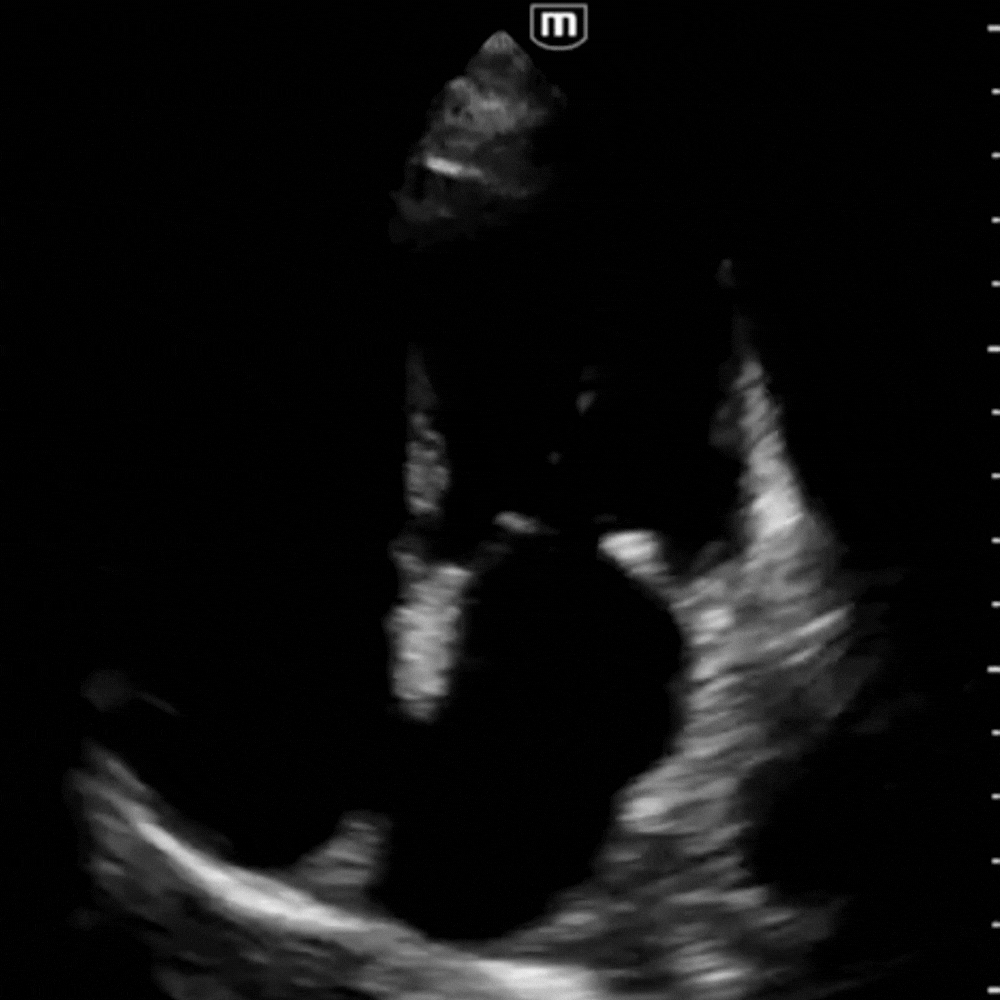

Vue A4C avec FEVG diminuée.

Vue A4C avec FEVG très diminuée.